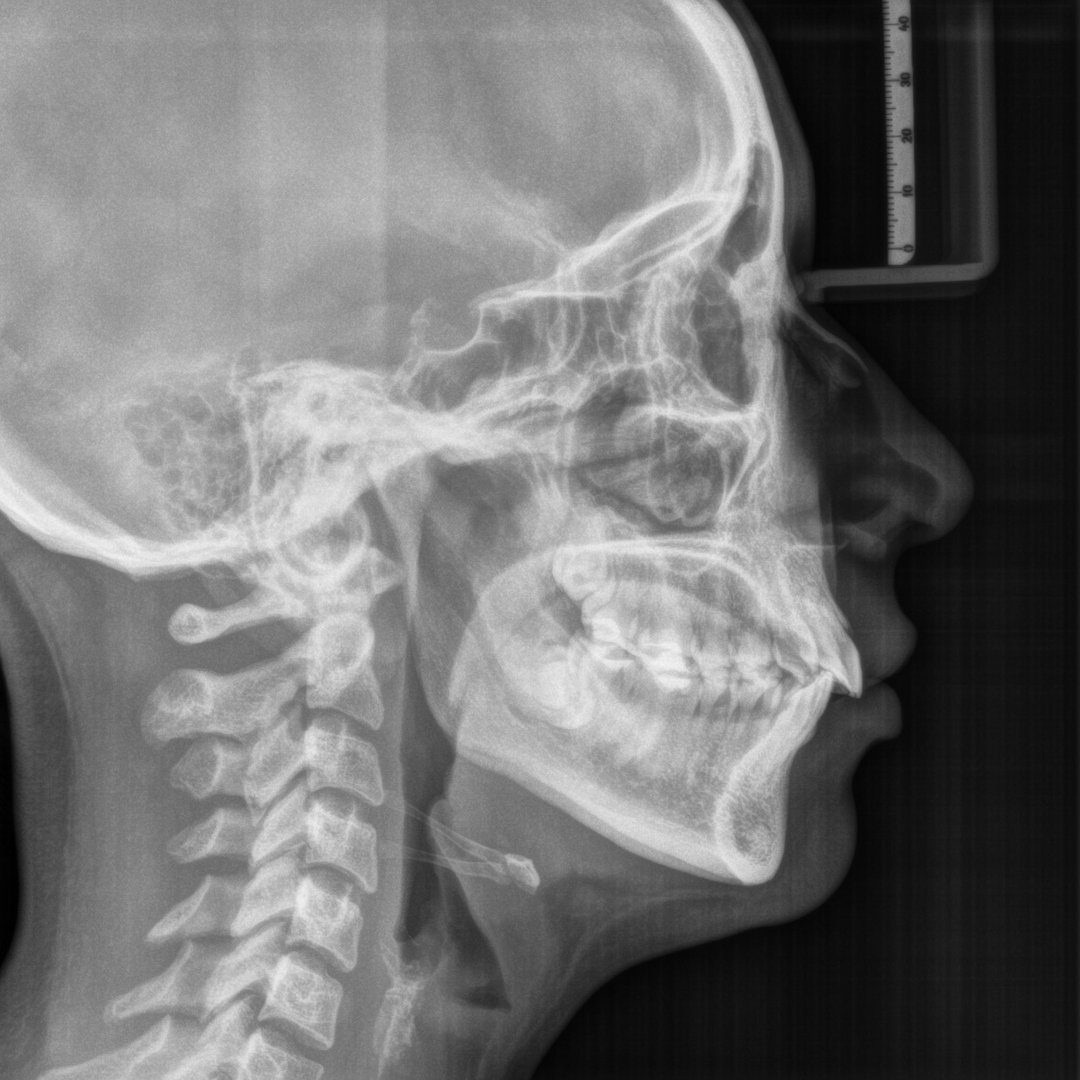

Estudios de Ortodoncia

Ofrecemos estudios ortodónticos completos para evaluar y planificar tratamientos ortodónticos efectivos. Incluye la radiografía panorámica, lateral de cráneo, fotografía clínica, modelos de estudio de resina y un trazo cefalométrico.